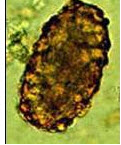

下图是哪一寄生虫卵()

A .受精的蛔虫卵

B .未受精的蛔虫卵

C .蛲虫卵

D .钩虫卵

E .鞭虫卵